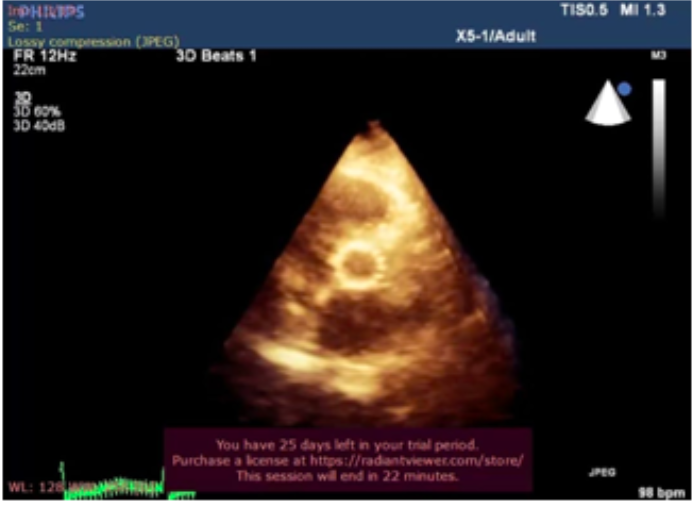

Məqalədə qulaqcıqların fibrilyasiyasının (QF) əmələ gəlməsində rolu olan qulaqcıqların struktur remodelləşməsinə və fibrozuna aid olan məsələlər müzakirə edilir.QF-nın əmələ gəlməsinin əsas risk faktorları ürəyin işemik xəstəliyi, arterial hipertenziya,mitral qapaq qüsurları ,ürək çatışmazlığı və bəzi ekstrakardial səbəblərdir. Əsas diqqət sol qulaqcığın (SQ) funksiyasını göstərən onun gərilməsi və deformasiyasına verilmişdir. Bu amillər SQ-ın nasos funksiyasının depressiyasında həlledici rol oynayır. Qeyd edilmişdir ki, SQ -ın genişlənməsi və onun miokardının fibrozu QF-nın əmələ gəlməsində xüsusi yer tutur. Qulaqcıq fibrozunun inkişafının əsas səbəblərindən biri isə lektin qrupundan olan fibroblastların aktivləşməsində və kollagen sintezində iştirak edən qalektin-3 hesab edilir.Bundan əlavə məqalədə fibrozun və ürək çatışmazlığının əmələ gəlməsində iştirak edən digər amillərə də , yəni renin-angiotenzin-aldosteron və TG F-β1 kimi neyrohumoral faktorların iştirakı da diqqətə çatdırılmışdır. Göstərilmişdir ki, aldosteron fibrogen amillərin sintezini tənzim edərək fibroblastların aktivləşməsinə gətirib çıxarır. Beləliklə ,fibrozun əmələ gəlmə mexanizmlərinin dərk edilməsi, onun markerlərinin təyin edilməsi ,QF prediktorlarının aşkar edilməsi QF -nın risk qruplarının vaxtında təyin edilməsinə və bu aritmiyanın profilaktikası üçün zəmin yaratmış olacaqdır.